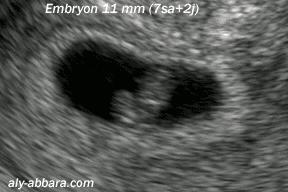

而母猪、母牛等则可以通过超声波检查等方法诊断妊娠情况。

此外,因胚胎着床太迟、腹中胎儿太小,工作人员也很难用超声波观察到。

一般来说,成年雌性大熊猫在产仔前的十几天,才能探测到其腹中胎儿。

有的怀孕大熊猫,甚至要到分娩前的一两天工作人员才能够真正断定它怀孕的真假。